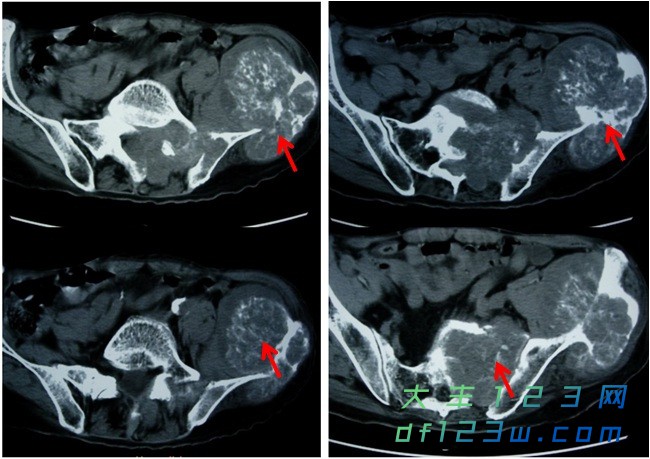

离休干部刘叔,今年80岁,15年前偶然发现左髂腰部一鹌鹑蛋大小肿物,无不适感,未引起重视。近1年来刘叔左髂腰部肿物增大明显,并伴有行走时间较长后左髂腰部酸胀感,近半年来刘叔出现了腰骶部疼痛的症状。一个月前,刘叔来我院检查,骨科医生要求刘叔做一个骨盆CT检查,骨盆CT检查发现左髂骨翼及左骶髂关节多发骨质破坏并软组织肿胀形成,其内可见不规则高密度灶。影像诊断考虑为左髂骨软骨肉瘤。一周前刘叔做了穿刺活检,活检结果是软骨肉瘤。